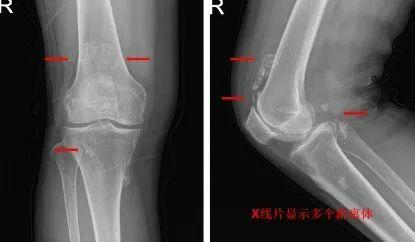

首先,对于“关节鼠”的诊断还是比较简单的,如果患者存在着突然的关节疼痛以及关节交锁的症状,那么进行X线检查就可以发现患者关节内是否存在骨性游离体了。当然对于有些特殊的情况,例如软骨在X线上不显影时,也可以进行核磁的检查,来进一步的明确关节腔内是否有软骨性游离体。